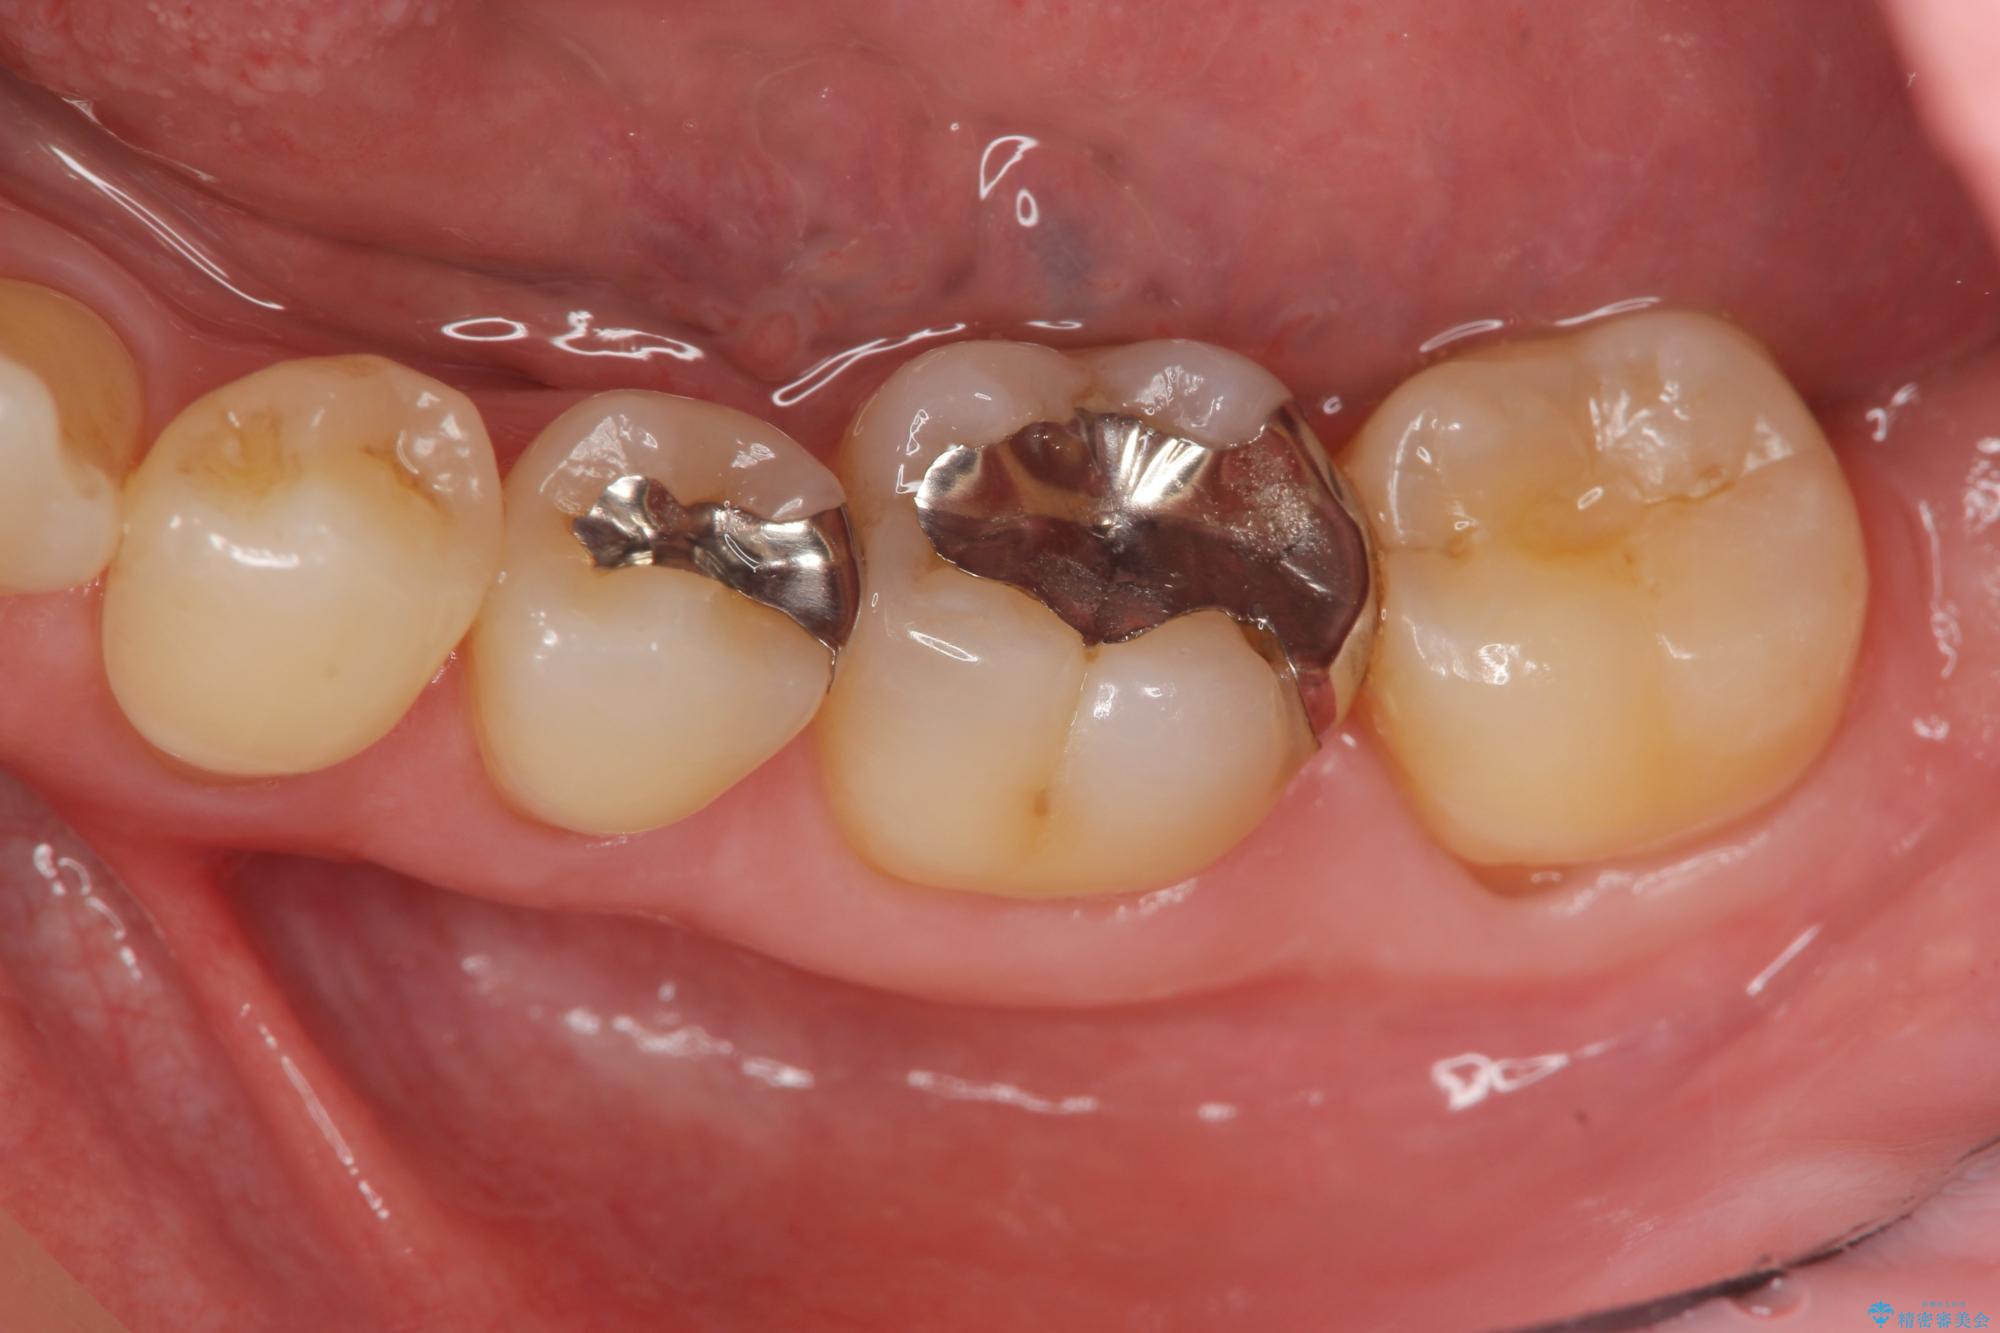

- 長年見た目が気になっていた銀歯のやりかえを希望されて来院されました。

銀歯を丁寧に除去し、セラミクインレーによる置き換えを行いました。

自然なセラミクの仕上がりに満足いただくことができました。